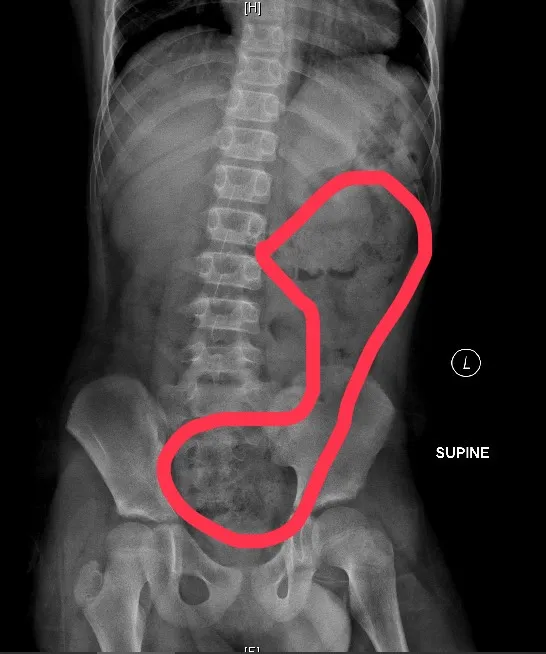

6歲女生X光片,畫圈部分為積糞。翻攝畫面